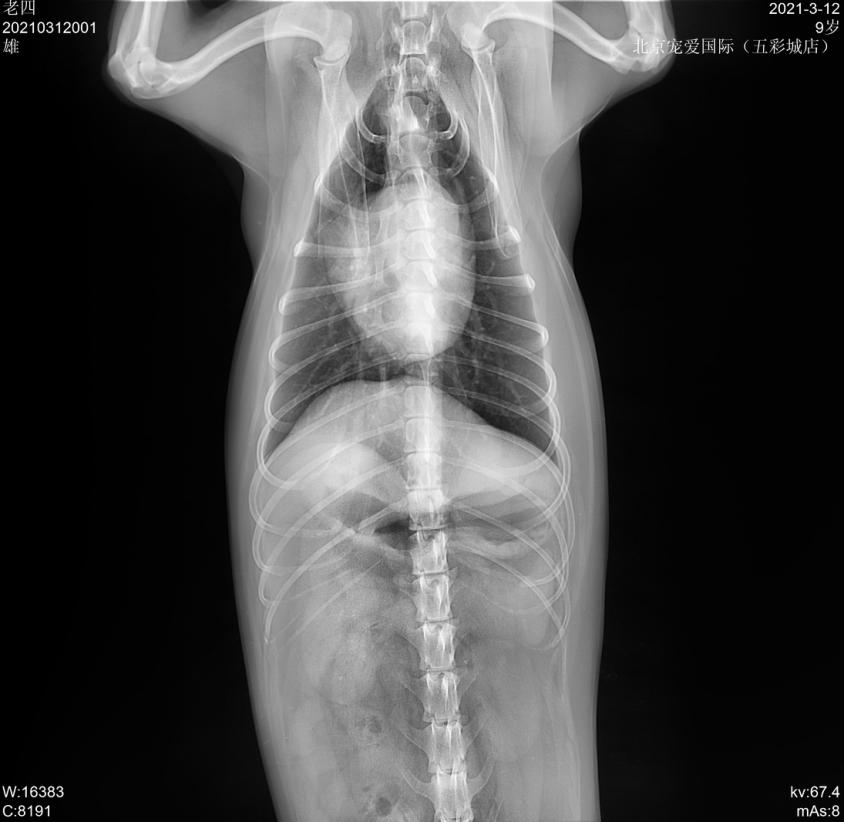

- 宠物名:老四

- 性别:男孩

- 年龄:8岁10个月

- 品种:喜乐蒂犬

- 体重:13.5KG

临床检查: TPR正常,精神沉郁,步态缓慢,肛门左侧有一大的鼓包,较软; 直肠检查肛周左侧有一疝孔。

x线检查

会阴疝